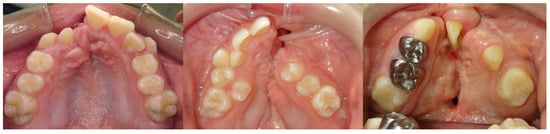

3.3. Step 3: Reverse Engineering the Transitional Occlusion